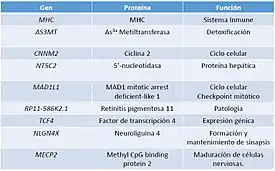

También se ha encontrado alta presencia de SNPs en el cromosoma 2 concretamente en C2orf69, C2orf47 y TYW5 y en otras 5 regiones como el locus del MHC (cromosoma 6) AS3MT-CNNM2-NT5C2 (cromosoma10), MAD1L1 (cromosoma 7), RP11-586K2.1 y TCF4 (cromosoma 18) y NLGN4X y MECP2 (cromosoma X).